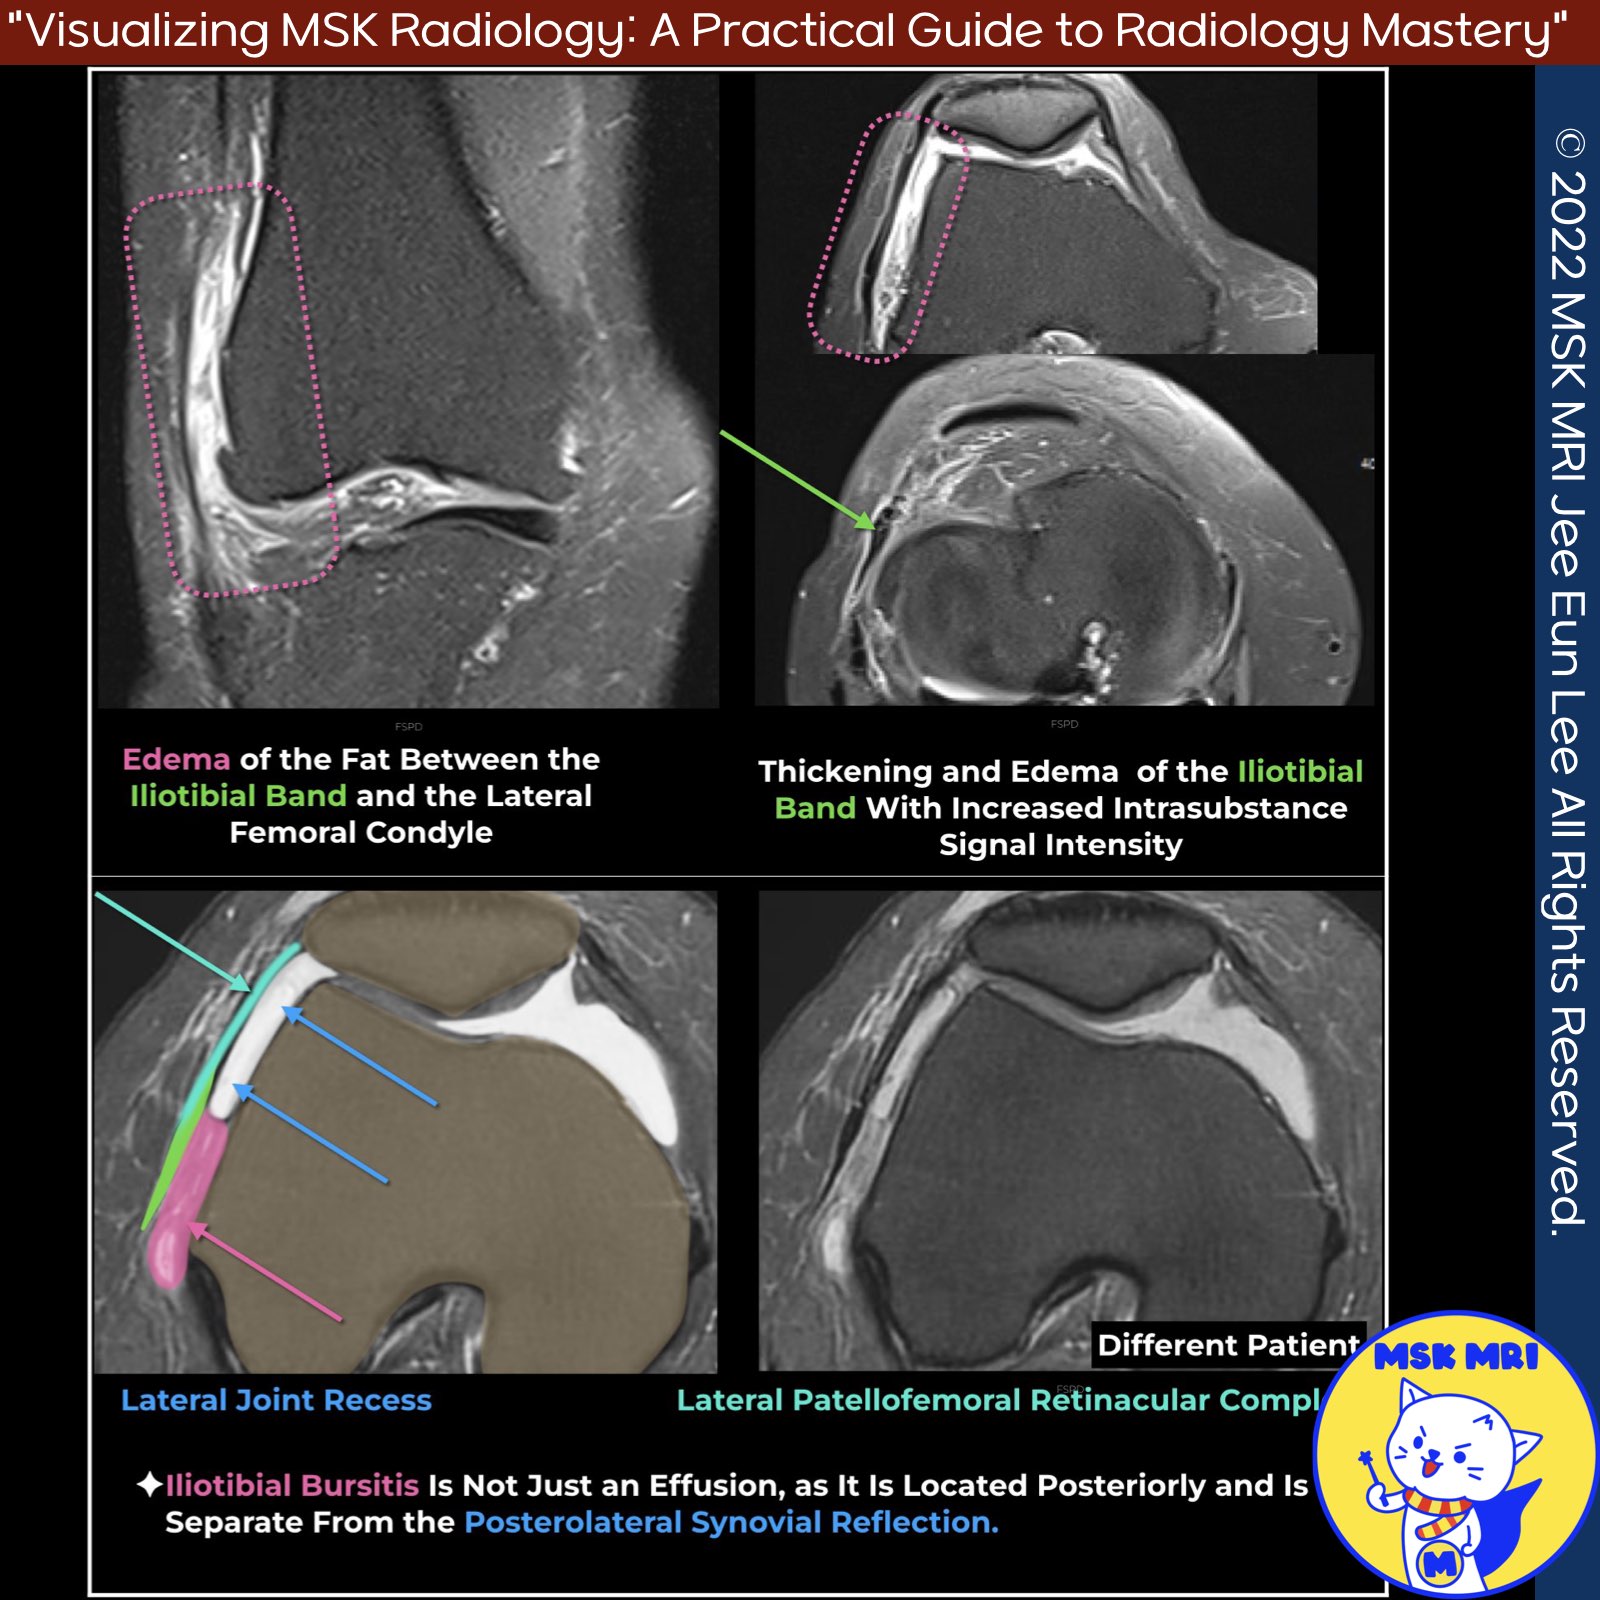

📌 Iliotibial Band Friction Syndrome

Iliotibial band friction syndrome is a common cause of lateral knee pain associated with intense exercise, such as long-distance running, football, and cycling.

It results from chronic friction between the iliotibial band and the lateral femoral condyle during knee flexion.

✅ MRI Findings

- MRI often shows ill-defined high T2 signal intensity or edema within a compartment-like space bounded laterally by the iliotibial tract and medially by the lateral femoral condyle, lateral meniscus, and meniscocapsular ligaments.

- Thickening of the iliotibial band may or may not be present.

- In some cases, a discrete fluid collection develops within the same space deep to the distal iliotibial band, representing adventitial bursal formation.

- Edema superficial to the iliotibial band is uncommon in friction syndrome and is typically associated with acute trauma.

- Thickening of the iliotibial band itself is usually not observed.